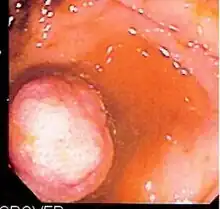

![]() Endoscopic image of normal small bowel | |